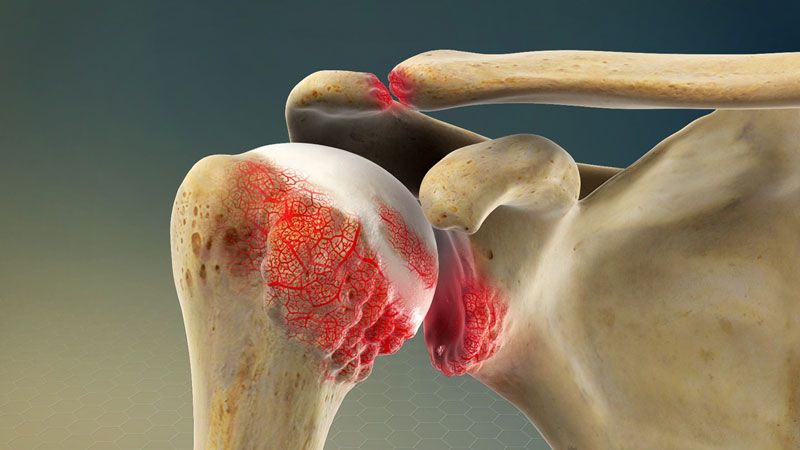

Viêm khớp

Khớp vai xuất hiện tình trạng viêm có thể khiến cho các tế bào hệ miễn dịch hoạt động gây nên triệu chứng sưng, nóng, đỏ và đau của khớp vai. Ngoài ra, tình trạng viêm khớp mạn tính như viêm khớp dạng thấp hay viêm xương khớp cũng khiến cho cấu trúc vùng vai bị phá vỡ và gây đau.

Viêm khớp có thể khiến cho vai bị sưng đau